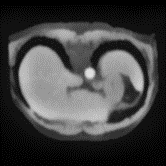

In clinical practice, well-aligned multi-modal images, such as Magnetic Resonance (MR) and Computed Tomography (CT), together can provide complementary information for image-guided therapies. Multi-modal image registration is essential for the accurate alignment of these multi-modal images. However, it remains a very challenging task due to complicated and unknown spatial correspondence between different modalities. In this paper, we propose a novel translation-based unsupervised deformable image registration approach to convert the multi-modal registration problem to a mono-modal one. Specifically, our approach incorporates a discriminator-free translation network to facilitate the training of the registration network and a patchwise contrastive loss to encourage the translation network to preserve object shapes. Furthermore, we propose to replace an adversarial loss, that is widely used in previous multi-modal image registration methods, with a pixel loss in order to integrate the output of translation into the target modality. This leads to an unsupervised method requiring no ground-truth deformation or pairs of aligned images for training. We evaluate four variants of our approach on the public Learn2Reg 2021 datasets \cite{hering2021learn2reg}. The experimental results demonstrate that the proposed architecture achieves state-of-the-art performance. Our code is available at https://github.com/heyblackC/DFMIR.